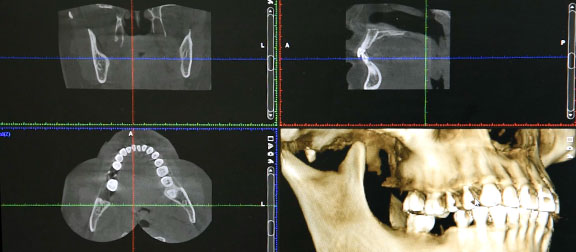

1. 3D CBCT CT imaging scan and 2D panormic x-rays

2. Computerized simluation and implant planning software to measure and provide proper diagnoses for implant placement

A panoramic x-ray and/or CT scan is taken during your first visit. The x-ray images are used to evaluate the amount of bone, determine the space available and for a thorough examination before your dental specialist diagnoses which type of dental implant protocol options is available or suited for you. Implant treatment time is thus significantly shorten. Dental implants has improved the quality of life for millions of people.